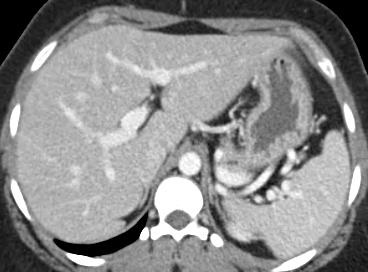

Case 3-F/U

In this retrospective study consisting of three patients, balloon-occluded retrograde transvenous obliteration (BRTO) can be a successful alternative treatment of gastric varices in patients with portal vein thrombosis who are ineligible for TIPS